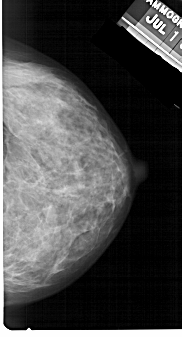

A_1392_1.RIGHT_MLO

RIGHT_MLO LINES 5491 PIXELS_PER_LINE 3136 BITS_PER_PIXEL 12 RESOLUTION 43.5 NON_OVERLAY